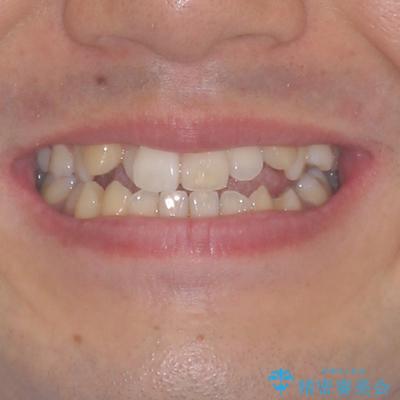

左右の八重歯が気になる ワイヤー装置での咬み合わせ改善

- 八重歯と前歯のデコボコを気にして来院された患者様です。

営業職であり、商談などで飲食をする機会が多いとのことで、インビザラインではなく、ワイヤー装置にて矯正治療を行うこととしました。